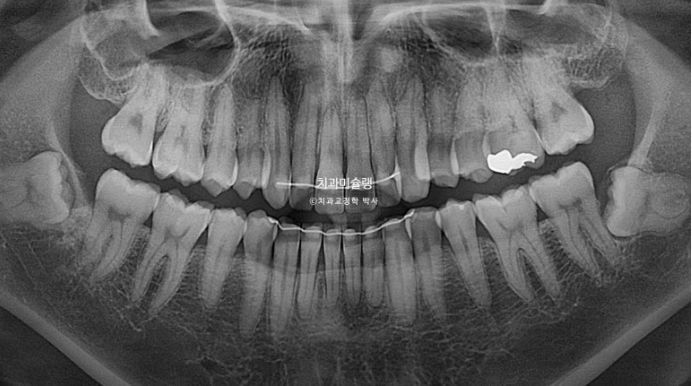

25.10

단기간에 필요한 최소한의 치아이동만 했으므로 치근흡수는 없었습니다.